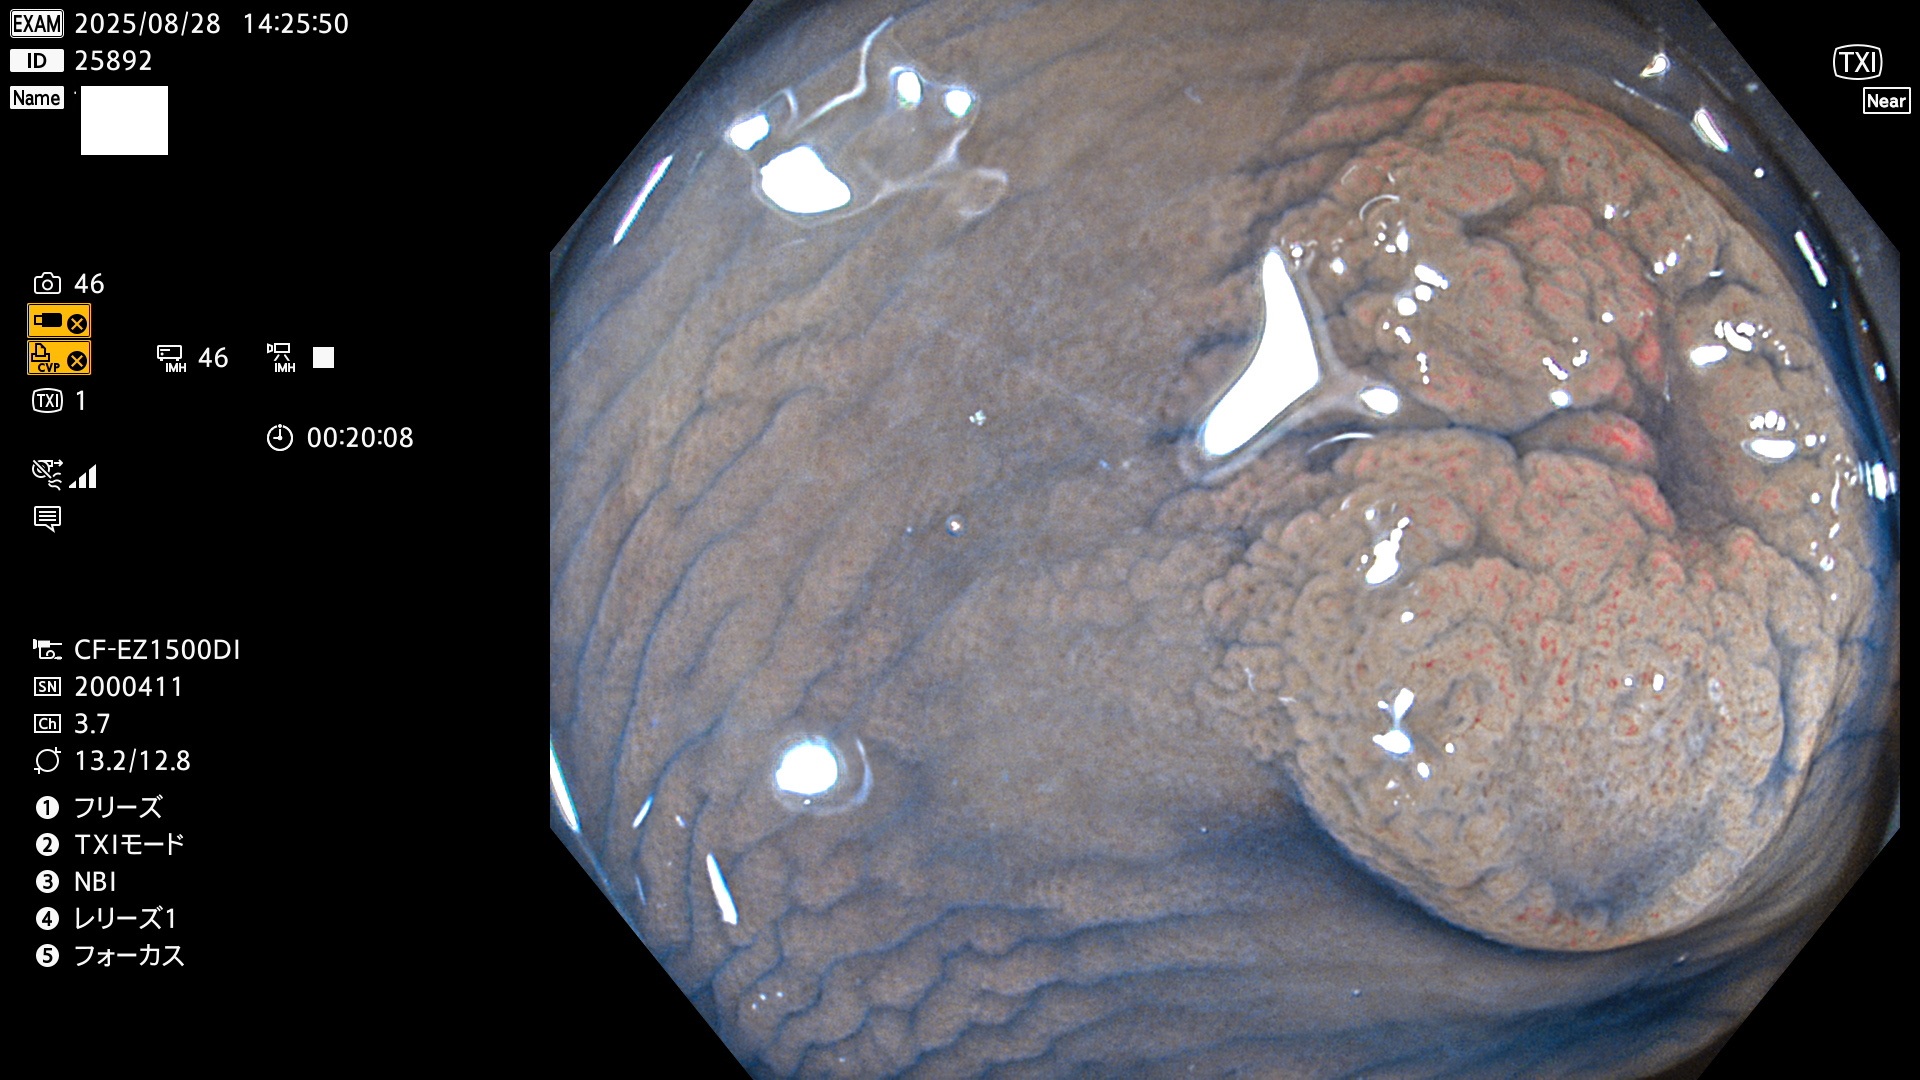

毎週の検査(木・金・土・日)に発見されたUbとUc型・腺腫を、その週の日曜の夜にUPし1週間、提示します。

写真公開の目的は「透明性・信憑性の担保」ですが、公開を希望されない方はメールで御連絡下さい。直ちに削除いたします。

2025年8月28日〜8月31日の4日間(30件)3個 (Uc_ADR=3個/30人=10%)